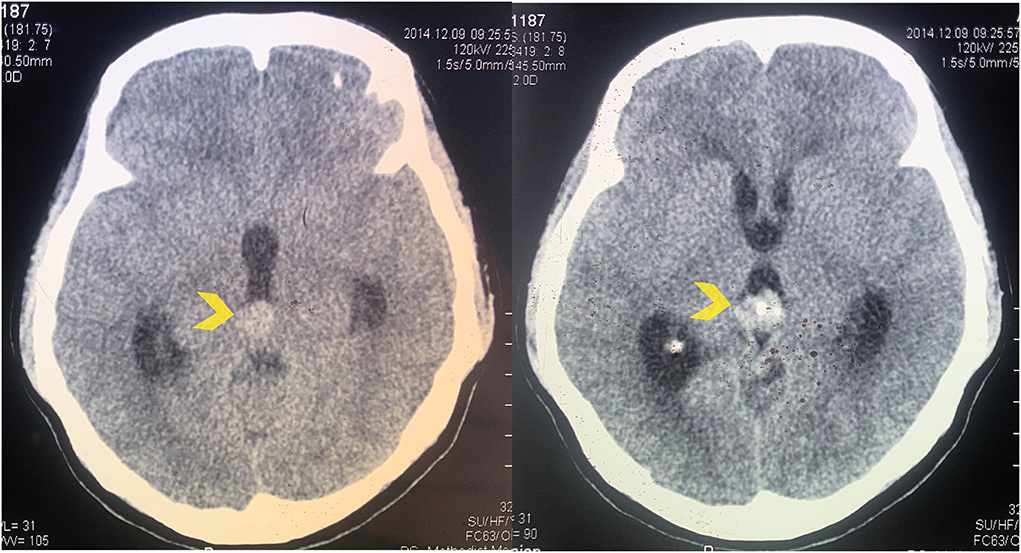

Computed Tomography (CT): Useful in detecting calcifications and assessing the presence of hydrocephalus or other structural changes in the brain.